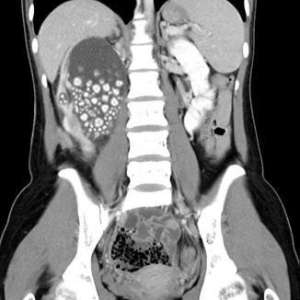

20-летняя девушка из Тайваня почти год не пила воду — только бабл-ти, соки и алкоголь. Когда начались боли в спине, УЗИ показало: в одной почке больше 300 камней, размером до 2 сантиметров.

Врачи сказали, что причина — обезвоживание. Сладкие напитки не заменяют воду, а только ухудшают работу почек.

Операция прошла успешно, но камни из почки доставали с помощью трубки почти час. Теперь она пьёт воду. Надеемся, вы — тоже.